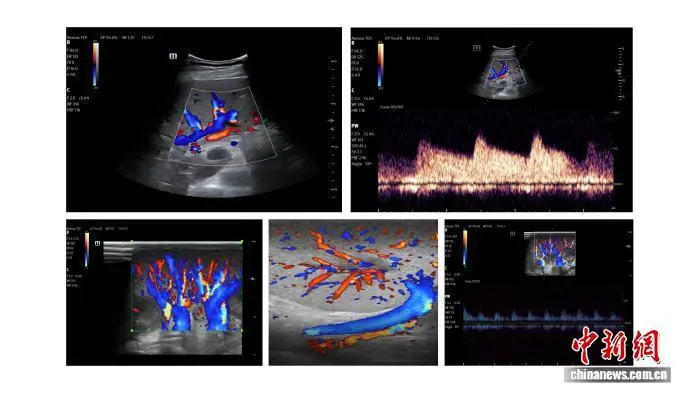

术后B超检查显示,移植肝脏、肾脏血流灌注良好。昆明医科大学第一附属医院 供图

肝脏移植采用原位辅助部分肝移植术式,是本次研究的核心环节。与国内外同类研究常用的全肝替换有所不同,该术式保留受者部分自体肝脏,让异种肝脏与自体肝脏在体内同步协同工作,更接近未来临床应用中“桥接治疗”的真实场景——用猪肝暂时替代衰竭肝脏功能,为患者自体肝再生或等待人源供肝争取时间。这一术式选择,体现了团队从“证明可行”到“怎么用更好”的前瞻思考。

手术团队先行切除受者左半肝,对供肝进行精细修整后,再完成血管吻合,吻合严格遵循肝脏解剖结构,完整重建门静脉、肝动脉的入肝血流通道。血流开放后,胆管内很快可见金黄胆汁流出,标志着移植肝脏开始发挥功能。

在连续11天的严密观察期内,移植肝脏胆汁分泌功能持续稳定,每日平均胆汁量超150毫升,单日最高超200毫升,接近正常生理水平,达到目前全球异种肝脏移植可见报道的最佳水平。

肾脏移植采用经典异位移植术式,血流开放后,移植肾即刻色泽红润,尿液自输尿管顺利流出。观察期内,移植肾脏尿量逐渐增多,总尿量达4000余毫升,单日最高超1800毫升,达到正常生理状态。